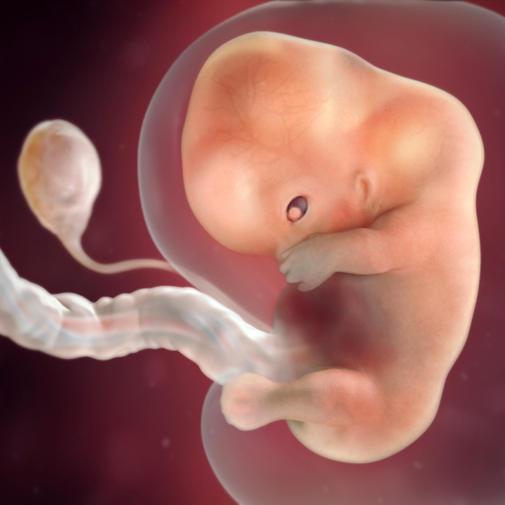

9. týden těhotenství je hlavová část zárodku ve srovnání s trupem značně veliká. Rovněž její ohnutí (souvisí s rychlým růstem mozku) až k srdečnímu hrbolu přetrvává. Trup a oblast krku se naopak trochu napřimují.

V obličeji se postupně srůstají jednotlivé výběžky. Dokončuje se vývoj nosu, který se zvedá nad úroveň obličeje. Vyvíjející se oči se přesouvají z postranní polohy dopředu a přibližují se k sobě. Oči jsou stále široce otevřeny. Základ brady je velmi široký, stejně tak i ústa. Kolem zevního zvukovodu se objevují hrbolky, které jsou základem ušního boltce. Rysy obličeje jsou nápadně hrubé.

V dutině břišní roste do délky tenké střevo a skládá se v kličky. Značné velikosti dosahuje v tomto období nad střevem uložený základ jater. Je tak velký, že na přední straně zárodku vytváří pod srdečním hrbolem další – jaterní hrbol. Velká játra vedou k napřimování dosud stočeného zárodku.

Nápadné jsou i změny na končetinách. Na horních se rýhy mezi prstovými paprsky ztenčují, takže základy prstů jsou nyní navzájem spojeny tenkými plovacími blánami. Na dolních končetinách se rýhy a prstové paprsky teprve zakládají.

Ocásek již téměř zmizel, zbytek ocásku zůstane jako budoucí kostrč.

Plod začíná vypadat jako lidské dítě, ale stále má tvar písmene C. Je vidět primitivní nos s dírkami. Objevují se první svaly. Vznikají oční panenky, čočka i sítnice a oční nerv začínají být funkční. Vyvíjí se pupečník, který bude po zbytek těhotenství komunikační tepnou mezi plodem a matkou. Poměrně rychle rostou jak horní, tak dolní končetiny. Na končetinách jsou patrné loketní ohnutí, na prstech se vytvářejí bříška. V následujících dnech se vyvine základ bránice – hlavního dýchacího svalu, které dítě začne využívat hned po porodu.

V 9. týdnu těhotenství měří plod zhruba 2,3 cm.Při zjišťování délky plodu se měří vzdálenost od temene ke kostrči. Váha plodu je nyní zhruba 2 gramy.